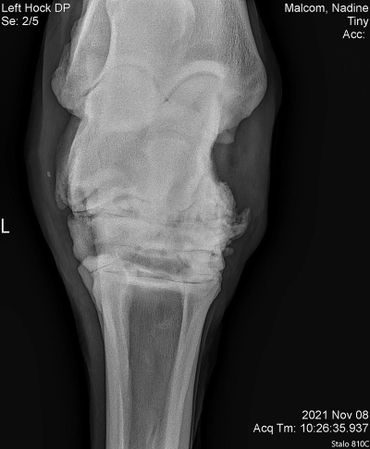

Tiny showed some stiffness in his left hind so we did x-rays on his hock on 11/09/2021. He's got some serious arthritis going on in there so he got injected to make him feel more comfortable especially with winter coming.

Now, three weeks down the road we enjoy seeing him move so much better and actually anticipating in the plays the geldings have with each other.

His vet bill was $585. Any contribution towards his bill would be greatly appreciated!